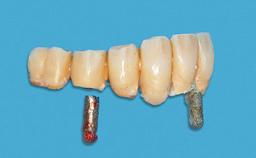

Early Implant Placement with GBR using DBBM

Early (Type 2) placement in a healthy, non-smoking male patient aged 28 years who required removal and replacement of the maxillary right central incisor due to external root resorption. A horizontal bone deficit requires a simultaneous augmentation procedure. The overall esthetic risk is high due to the horizontal bone deficit, medium to high lip line with exposure of the soft tissue margin when smiling, and the patient’s high esthetic expectations.

After flapless tooth extraction and a healing period of 6 weeks, a standard-diameter one-piece implant is placed. A gap between the implant and the facial bone wall is filled with autogenous bone chips harvested from the anterior nasal spine and covered with DBBM particles. Contour augmentation on the facial aspect is achieved using DBBM particles and a collagen membrane, according to the principles of guided bone regeneration (GBR). The flap is coronally repositioned for semisubmerged healing.